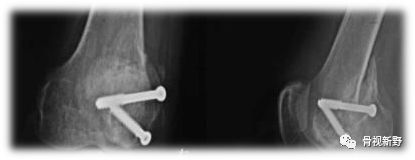

传统螺钉(小直径普通螺钉埋头或无头加压螺钉)固定(PA)。

传统拉力螺钉(小直径螺钉或无头加压钉多枚、埋头、PA打入)加buttress钢板进行固定[JM Shi 2013]。